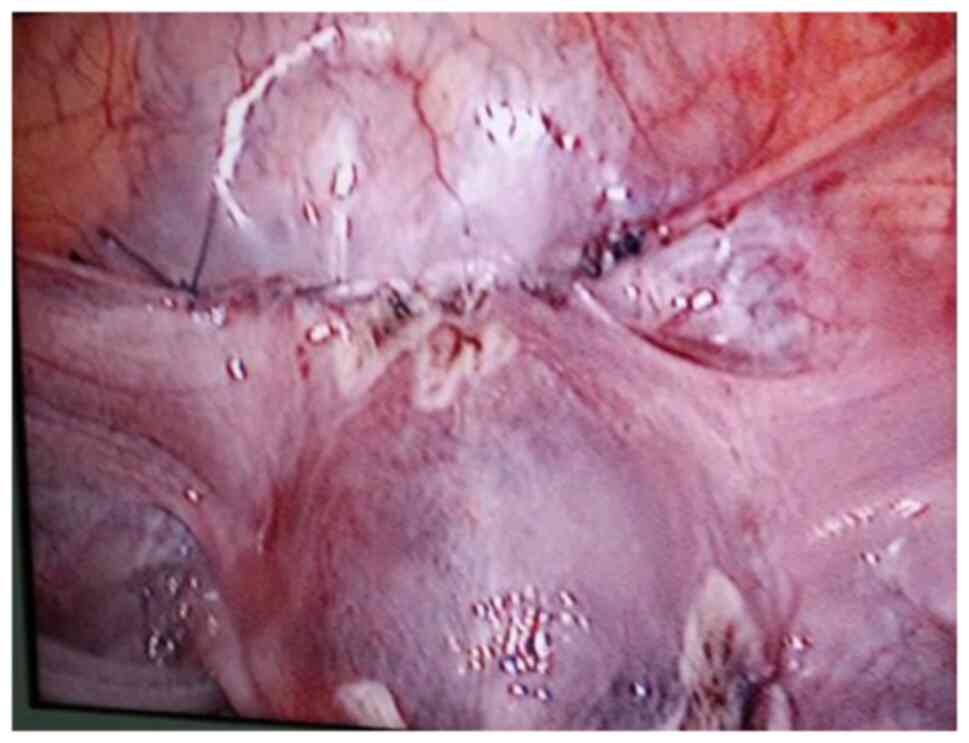

The surgical procedure was as follows: Laparoscopy was performed under general anesthesia in the supine lithotomy position. Laparoscopy displayed a bulging in the lower uterine segment (Fig. 1). Subsequently, a 12 IU vasopressin solution was injected into the uterus. The bladder peritoneum was incised to expose the pregnancy scar; a bulging was noted comprised of blood vessels and gestational tissues. The gestational tissue was rapidly removed with grasping forceps, scissors and an aspirator (Figs. 2 and 3). This procedure was performed as quickly as possible. The myometrial scar was resected and stanched by bipolar coagulation. Finaly, a continuous suture with an absorbable suture (1-0) was used to close the uterine wound (Fig. 4).

Figure 2

Opening of the bladder peritoneum and application of the pressure to the bladder (patient 5).

Figure 3